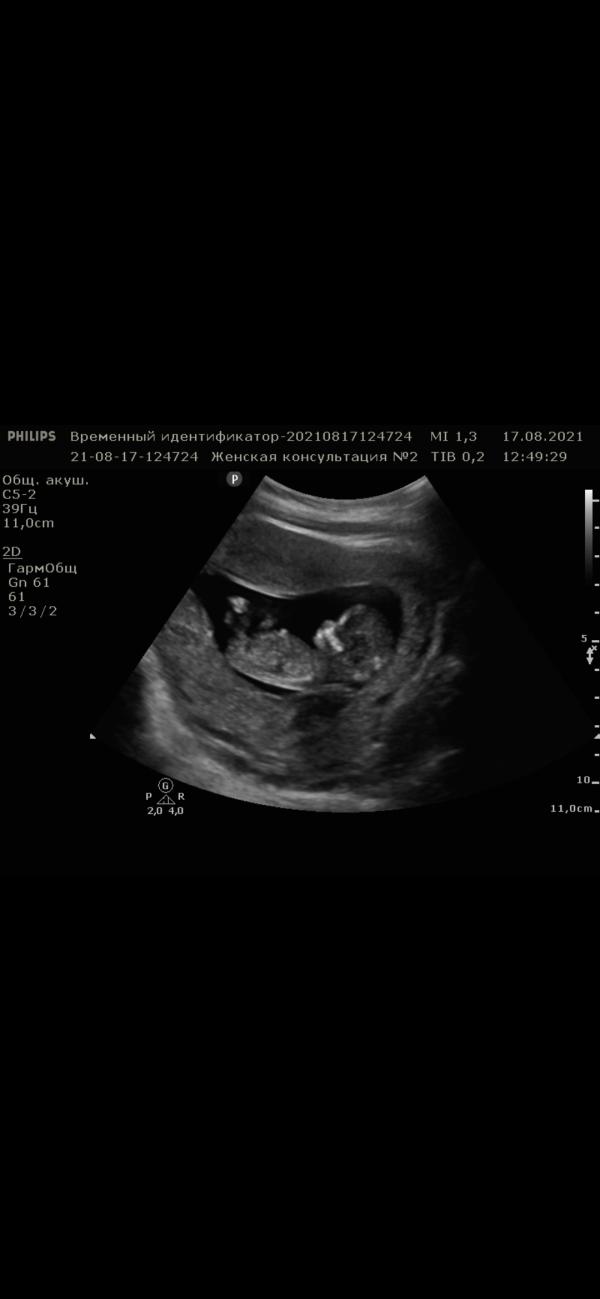

Наш первый скрининг😍 Такое чудо🥰 Все время смотрю и не как не налюбуюсь😅😍

Я конечно не специалист, но моя узистка говорила, что мальчики они более лобастве в этот срок беременности. Как на вашем фото 📷 похож на мальчика. Вам кого предположили?